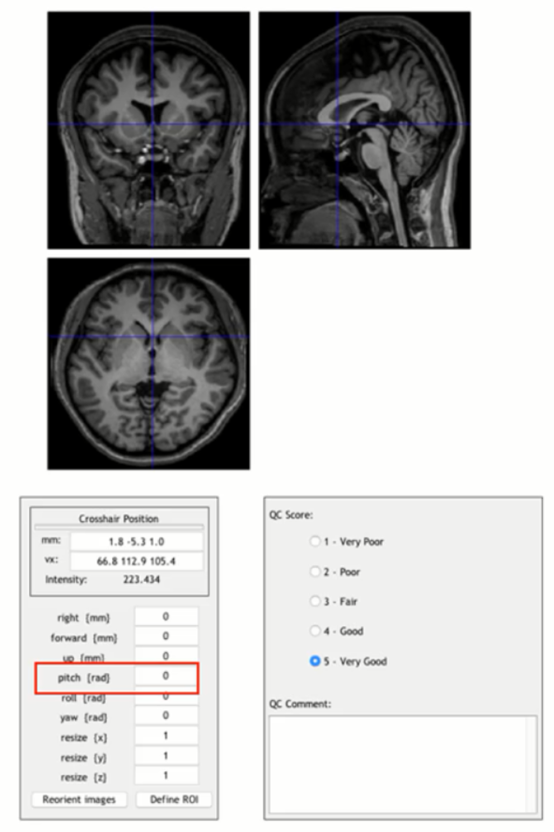

如果选择了这两项,在跑程序中途会弹出这样的界面(一个是功能像一个是结构像):

上面两张图所示被试的大脑位置和标准模板是差不多的,如果差得比较多可以通过左下的一系列参数进行调整,另外还需要把蓝色的十字架中心放在前联合的位置(和上图蓝色线所示的位置差不多),以配准原点,这一步直接用鼠标在图上点就可以。右下角QC score是对这个扫描图像的评分/评价,比如这个被试是否长了肿瘤,扫描有没有什么问题等等都可以选择评分,并进行备注,后面会专门生成一个QC文件以方便查看每一个被试的信息。最后按“Reorient image”即会自动跳到下一个被试图像。

这个功能好处是可以一个个被试进行查看并手动调整歪了的图像,但缺点是这一步会在中途直接跳出调整图像的询问窗口,如果不一个个看完就无法进入下一步。当被试太多时,每个功能/结构像都要单独看一遍,消耗的时间较长。因此若手上的数据已经初步看过或已经知道数据基本没有问题的情况下,可以直接跳过这两步。当然如果有被试的图像如下图,与标准模板相差极大,就必须执行手动调整。